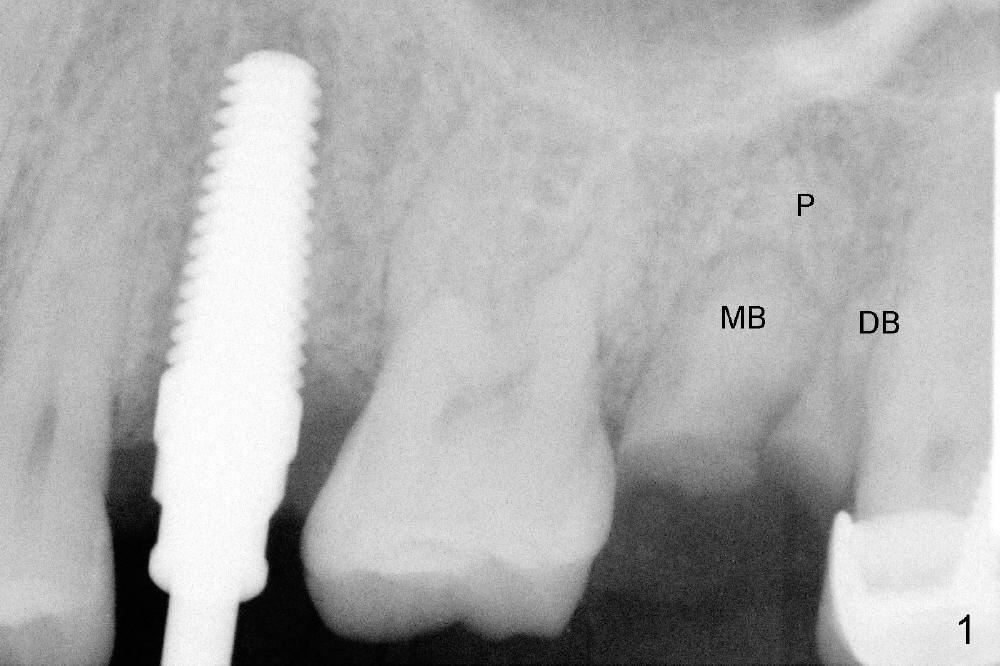

A 43-year-old lady has multiple nonsalvageable teeth. The first surgery involves two immediate implants in the upper left sextant (Fig.1: #13 and 15). The tooth #15 has 3 residual roots (MB, DB, P). There is no septum left between the first two roots when the tooth is extracted. A septum exists between the palatal (P) and buccal (B) sockets (Fig.2). Bone expansion technique is utilized to create an osteotomy in the septum. However, the smallest rounded tapered osteotome cannot be driven into the narrow septum; it slides (Fig.5). To get an initial engagement, a slot is created by high-speed surgical handpiece and fissure bur on the top of the septum. A series of blade-like osteotomes are inserted into the septum for sectioning (Fig.2 >). The smallest rounded osteotome is now easy to be inserted into the middle of the septum (Fig.3 circle, Fig.6 O). The septum is expanded by larger osteotomes (Fig.4 white circle; Fig.7 O) and tap (Fig.9 T). The septum continues being expanded when a 6x14 mm implant is placed (Fig.8,10 I). The insertion torque is more than 60 Ncm. No bone graft is placed. The palatal gap is closed by a palatal flap.